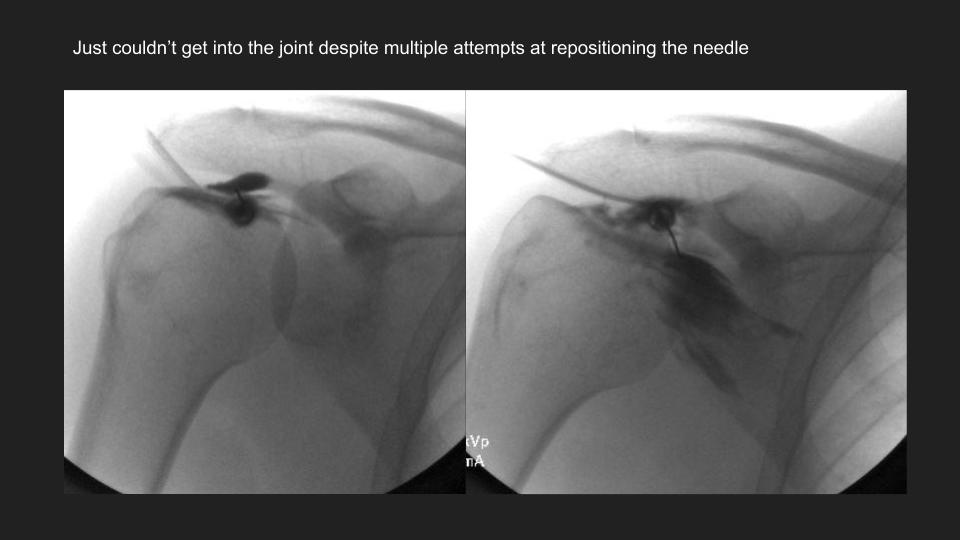

My colleague had to share this with me after a failed attempt at arthrography. He puts the shoulder in Grashey, but it doesnt really look like Grashey. No matter what, he couldnt get in and converted it to a routine MRI. The first set of Cor images look so nice....or do they? The crazy thing is that the injury was 3 years ago. Not all workers comp is bogus. I was taught the posterior shoulder dislocation locks the shoulder in internal rotation, but based on the axial image, it is not. 1) Why is that? 2) I think thats partly why the scout image for the arthrogram was so misleading.

dislocation ( RID4770 )